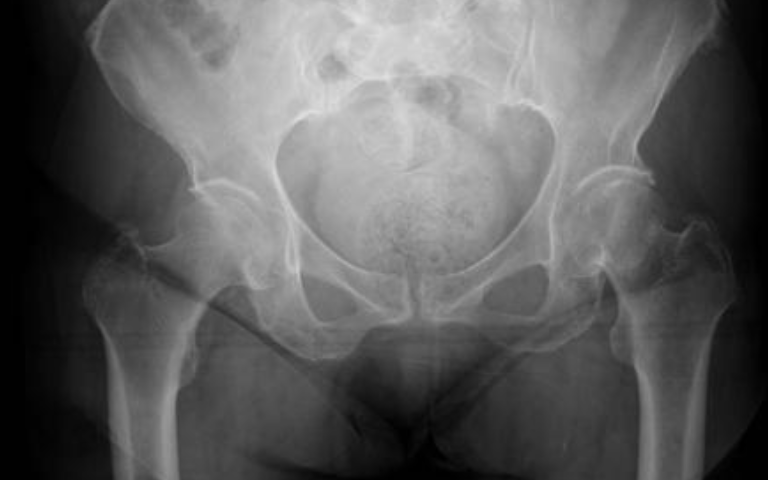

Hip fractures commonly occur in older adults due to weakened bones, as well as in younger patients following high-impact trauma. Symptoms include severe hip or groin pain, inability to stand or walk, and visible shortening or rotation of the leg. Accurate assessment through X-rays, CT scans, and clinical evaluation ensures a proper treatment plan and helps determine the need for hip fracture surgery in Islamabad.